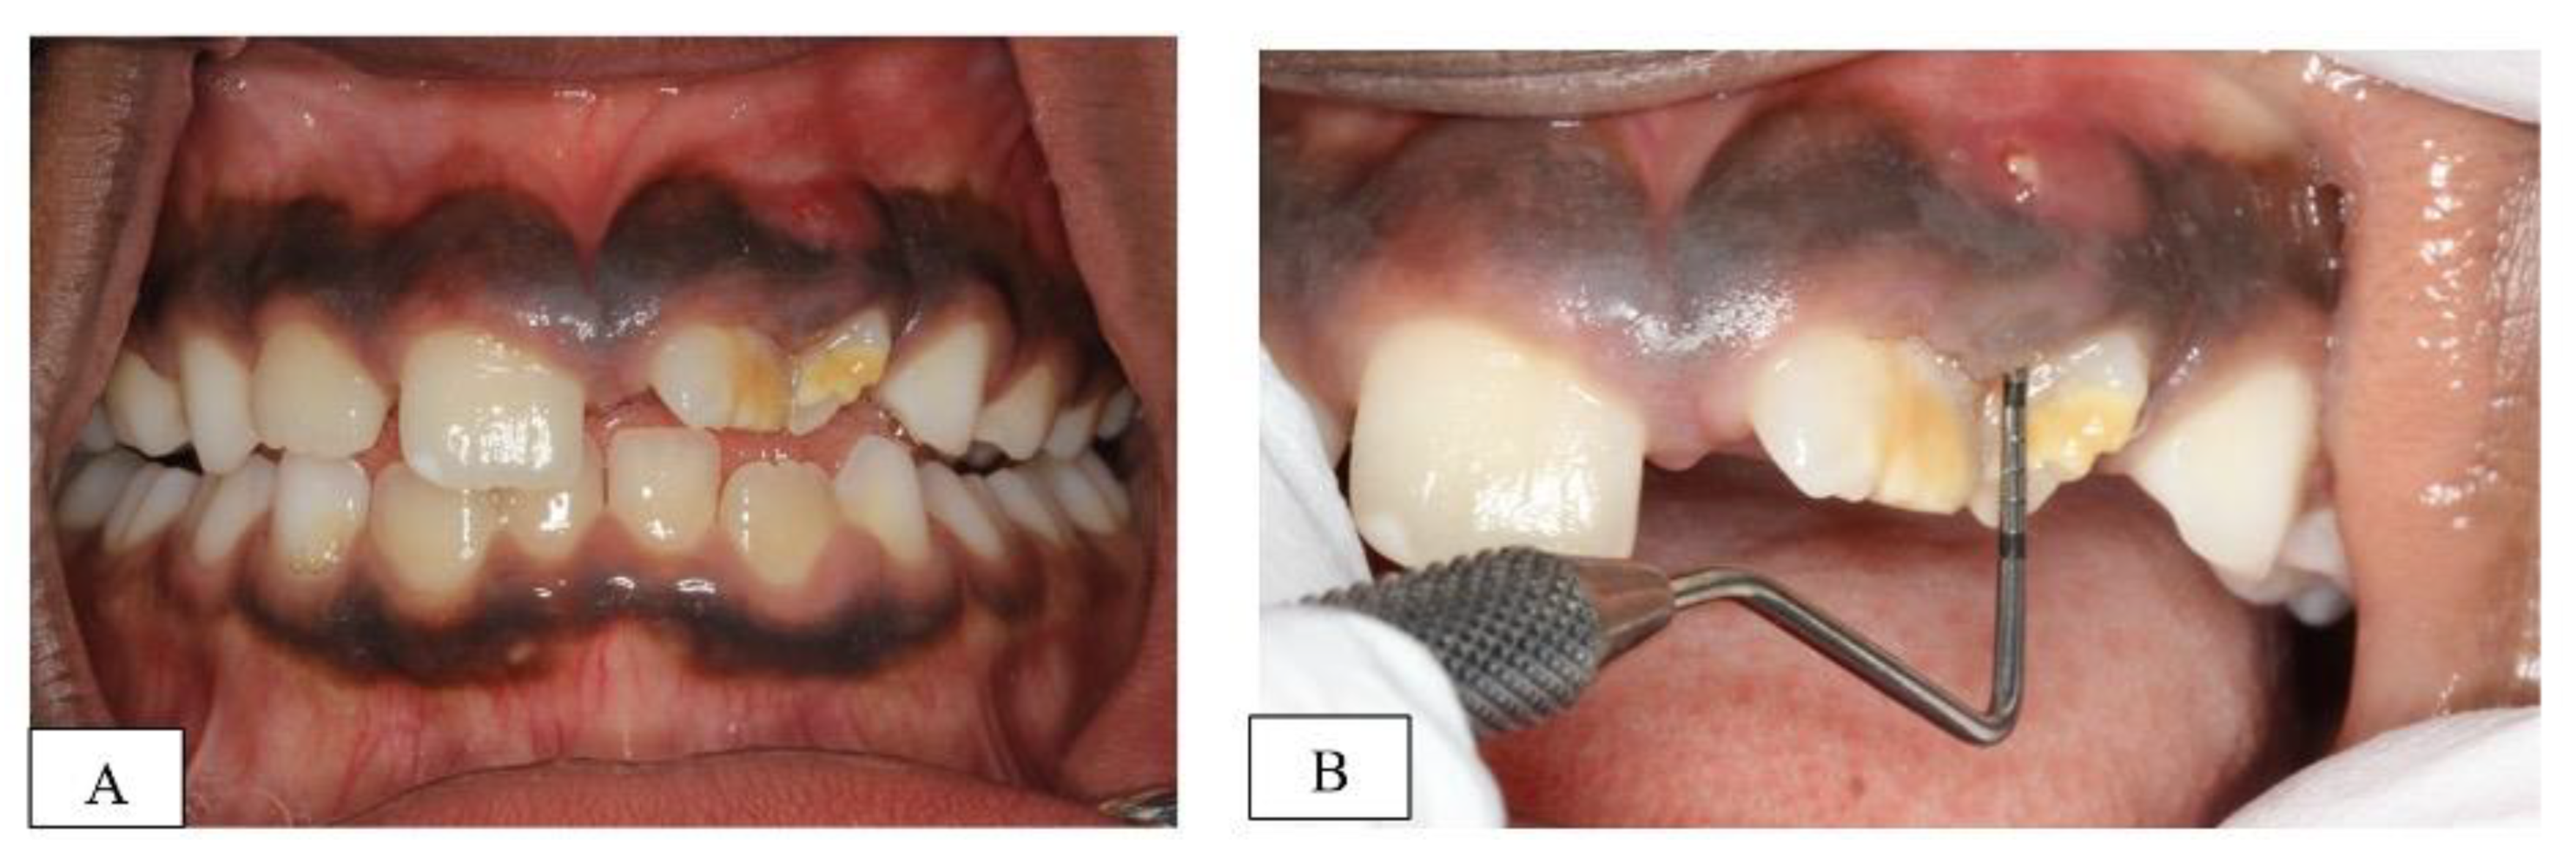

Clinical examination revealed hypoplastic enamel defects and malalignment of the upper left permanent incisors (teeth # 21&22) with a labial sinus tract between the two teeth (Figure 1A). An increased probing depth, in line with the sinus tract, was also recorded between the two teeth (highest reading 9 mm mid-buccal of 22) (Figure 1B). However, the teeth responded positively to cold sensibility testing with ‘Endo-Frost’ (Roeko; Coltene, Germany), had normal mobility and were not tender to percussion. The child had otherwise intact and caries-free dentition with no previous dental treatment.

Figure 1.

(A): frontal clinical view of patient’s dentition at initial assessment, (B): closer view of the hypoplastic teeth (21&22) showing the labial sinus tract and the increased probing depth (9 mm).